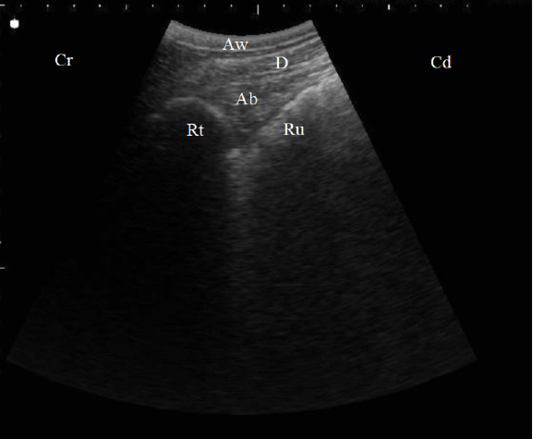

B. Mode ultrasonographic image in a healthy cow. Echogenic half-moon shape reticular wall (Rt) and the cranial dorsal ruminal sac (Ru) imaged from the left 6th ICS, the abomasum (Ab) appeared as a heterogenic structure with echogenic abomasal folds between the reticulum and the diaphragm (D), Aw: Abdominal wall, Cr: Cranial, Cd: Caudal.